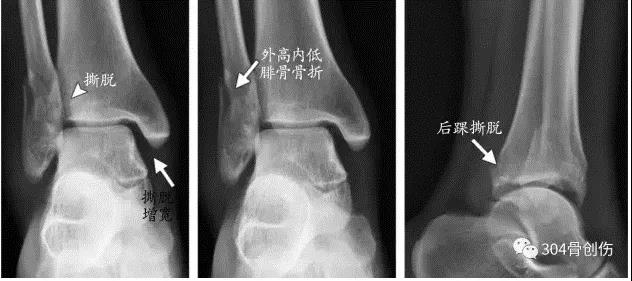

下胫腓联合损伤诊断

术中判断外旋应力试验::内侧间隙增大超过2毫米提示损伤Hook test:在内外踝骨折固定后,用尖钩向外拉腓骨,如腓骨向外移动大于4mm,则表明下胫腓联合韧带完全撕裂